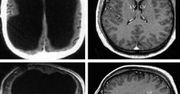

54-latek nie ma mózgu. Pracuje jako urzędnik

Myśleliście, że mózg jest niezbędny człowiekowi do życia? Nic bardziej mylnego. Ten mężczyzna żyje 54 lata bez mózgu i doskonale sobie radzi.